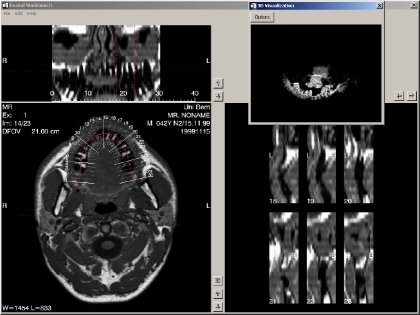

(2)IDL在牙齿植入中的应用

瑞士伯尼尔的Inselspital应用IDL5.4开发了一套软件用于牙齿植入计划,此软件可以实现轴切面的多平面显示,牙齿拱形弯曲的水平和垂直显示,骨结构的三维可视化,这些都可以辅助术前植入位置的决策。并且支持MRI(核磁共振成像)的数据,使得病人远离放射的困扰。IDL自带的大量函数和面向对象的编程概念,节省了软件开发的时间,并且可以方便的对系统进行更改和新功能的植入。

Fig2-1:应用IDL开发的牙齿植入辅助软件功能示意图